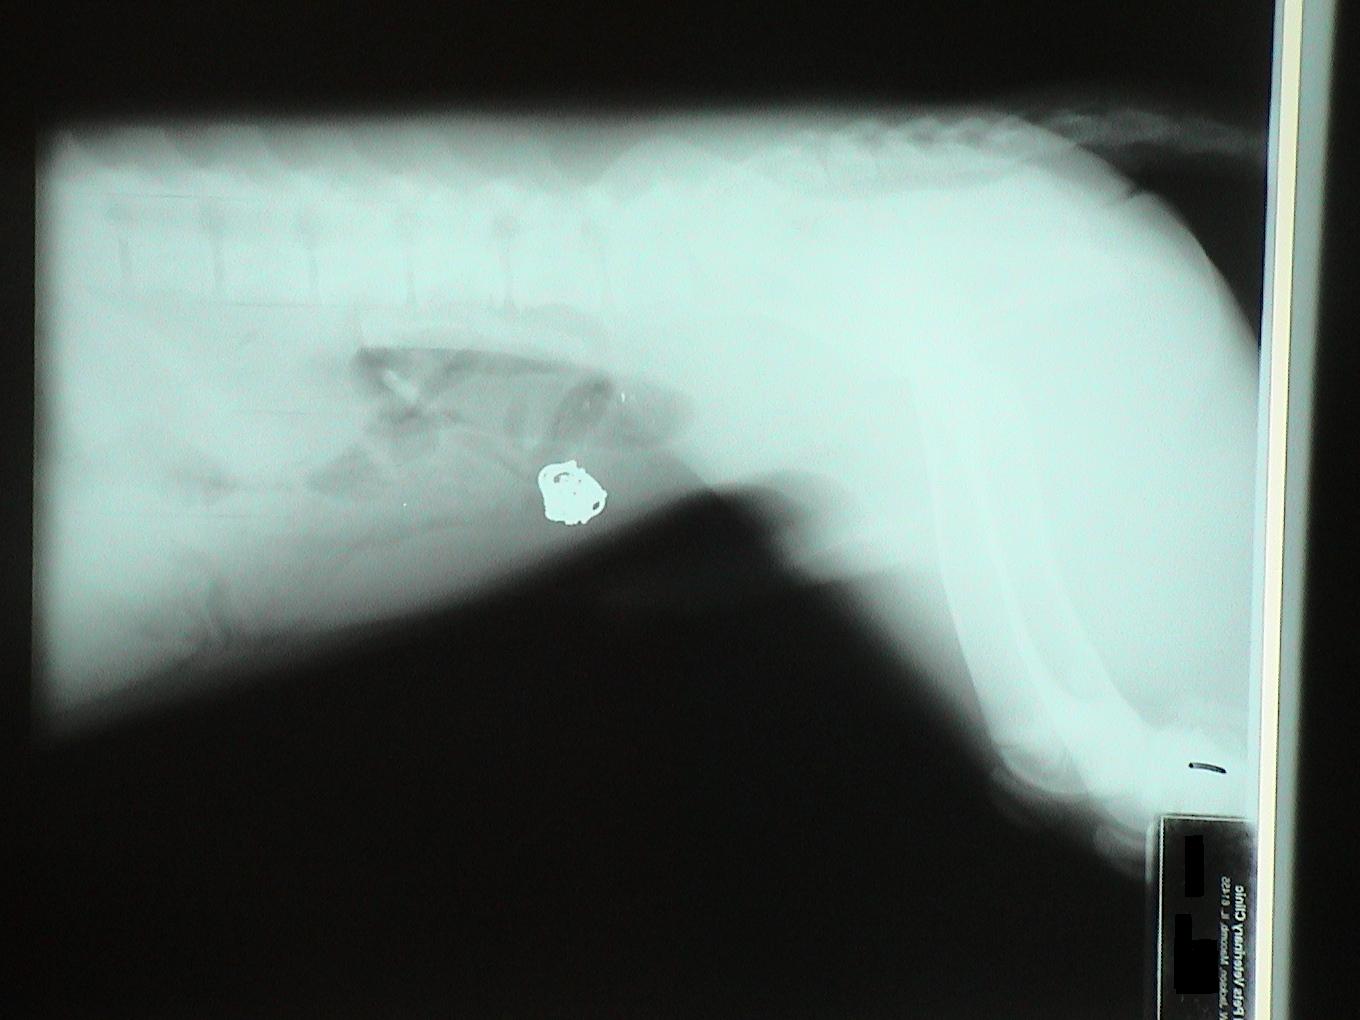

Let's identify the foreign bodies in each of these x-rays.

This is a trick question. This is a pregnant dog. Each skull is circled in blue.